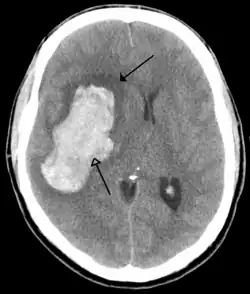

The main risk factor for stroke is high blood pressure.[6] Other risk factors include tobacco smoking, obesity, high blood cholesterol, diabetes mellitus, a previous TIA, end-stage kidney disease, and atrial fibrillation.[2][6][7] An ischemic stroke is typically caused by blockage of a blood vessel, though there are also less common causes.[12][13][14] A hemorrhagic stroke is caused by either bleeding directly into the brain or into the space between the brain's membranes.[12][15] Bleeding may occur due to a ruptured brain aneurysm.[12] Diagnosis is typically based on a physical exam and supported by medical imaging such as a CT scan or MRI scan.[8] A CT scan can rule out bleeding, but may not necessarily rule out ischemia, which early on typically does not show up on a CT scan.[9] Other tests such as an electrocardiogram (ECG) and blood tests are done to determine risk factors and rule out other possible causes.[8] Low blood sugar may cause similar symptoms.[8]

Stroke is diagnosed through several techniques: a neurological examination (such as the NIHSS), CT scans (most often without contrast enhancements) or MRI scans, Doppler ultrasound, and arteriography. The diagnosis of stroke itself is clinical, with assistance from the imaging techniques. Imaging techniques also assist in determining the subtypes and cause of stroke. There is yet no commonly used blood test for the stroke diagnosis itself, though blood tests may be of help in finding out the likely cause of stroke.[63]

CT scans may not detect an ischemic stroke, especially if it is small, of recent onset, or in the brainstem or cerebellum areas. A CT scan is more to rule out certain stroke mimics and detect bleeding.[9]